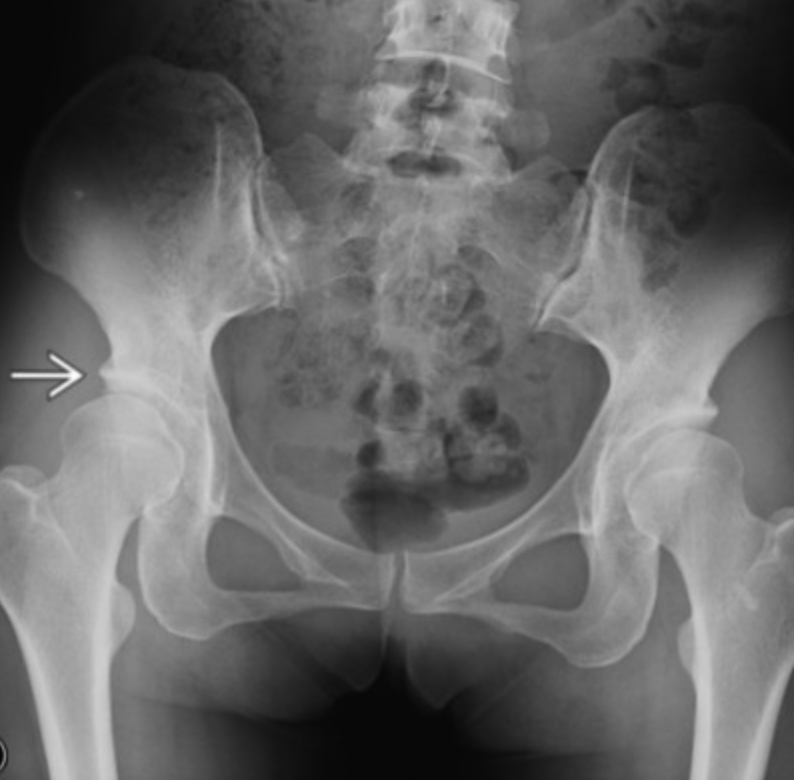

Slipped Capital Femoral Epiphysis

• Fat kids

• ~12 years old

• More often bilateral (30%)

• AA >caucasian

Klein Line

• Line drawn along superior edge of the femoral neck

• Should intersect the superior aspect of the femoral epiphysis

• If does not then concerning for SCFE